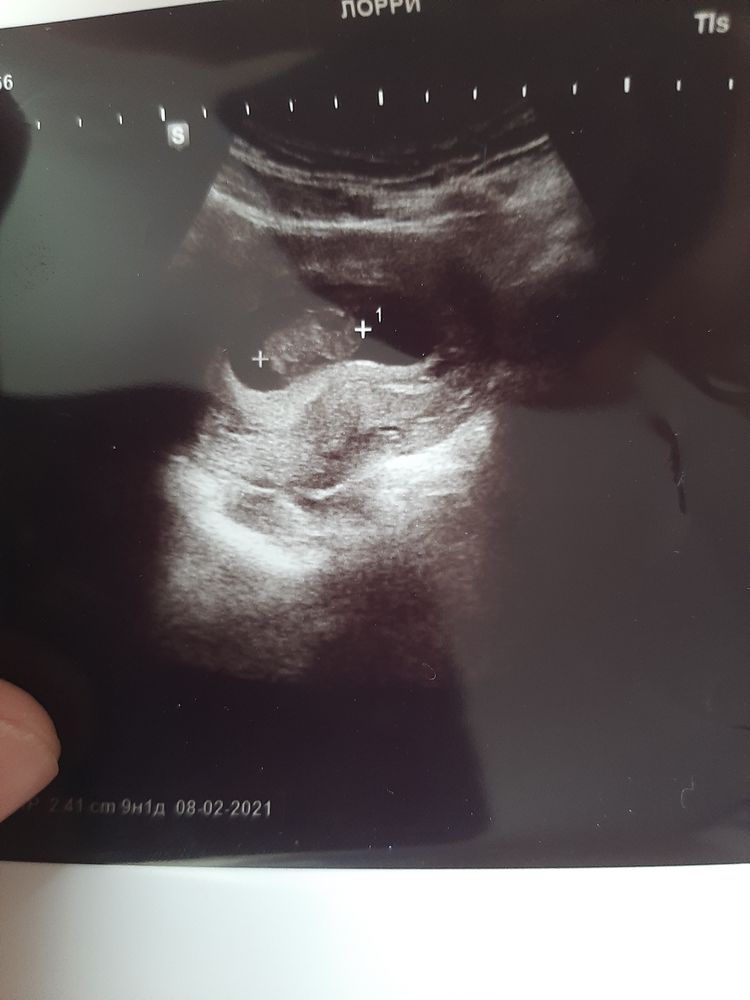

А вот моя кроха😈⬇️

Но ктр 5 дней назад был 19 мм, а сейчас 24 мм😍🤣

Сердцебиение все такое же - 144 ударов 🙈

Хорион по передней стенке (как и в прошлый раз)

Срок поставили 9+1. А акушерский срок 9+4. Все чётко, овуляция поздняя была, поэтому несколько дней нормально, врач также сказала😍❤